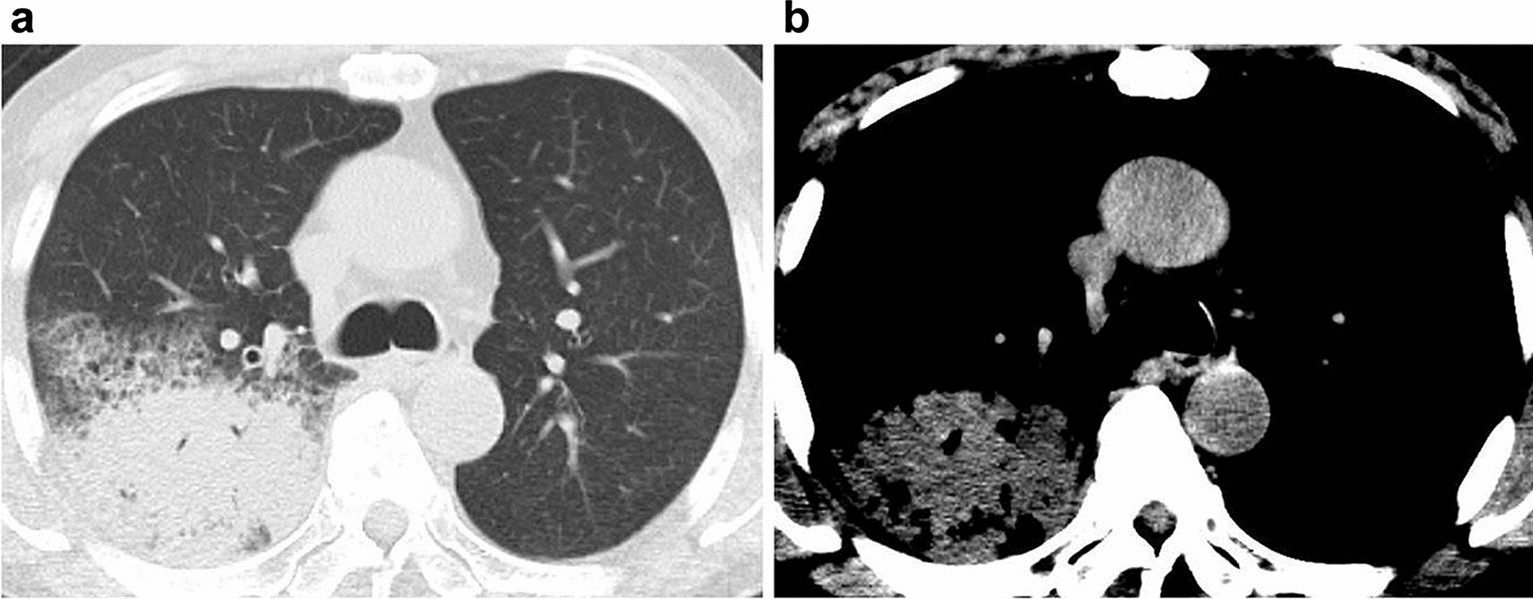

Figure 4

77-year-old man with bacterial pneumonia. (a) Transaxial CT with a lung window setting showing consolidations in the right lung. (b) In the narrow window setting with a mediastinal filter, the consolidation is iso- to slightly hypodense relative to the density in the aorta, indicating that the findings are negative for the hyperdense consolidation sign.